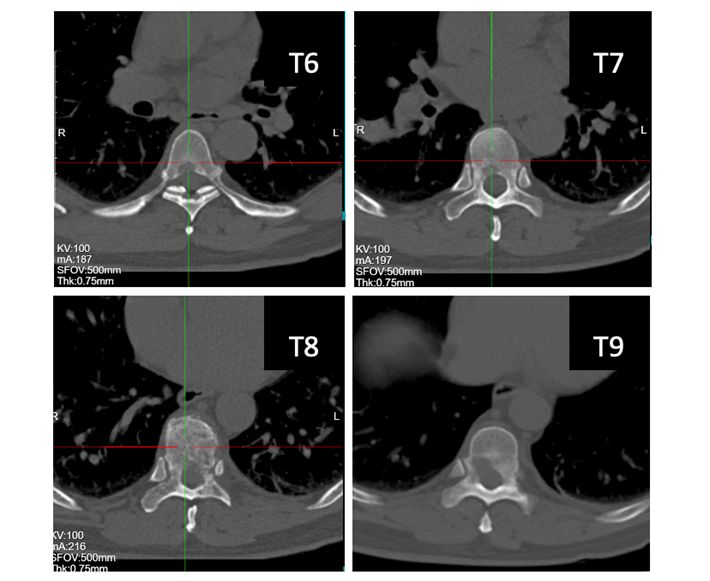

患者男性,62岁,半年前无明显诱因出现胸背部剧烈疼痛,伴下肢无力,严重影响了正常生活。就诊福建当地医院,胸部CT示:右肺下叶前基底段占位,右肺上叶后段类结节样影;T6-9椎体及部分附件多发骨质破坏。骨显像结果示:T6-9椎体显像剂摄取增高,考虑骨转移可能。遂于当地医院行肺部穿刺:(右下叶外基底段活检)结合免疫组化结果倾向腺癌。患者为行进一步治疗,至我院门诊收入病房。

1.T6-9胸椎继发恶性肿瘤(VAS 8分,SINS 11分, ESCC 1c,Tomita 6分,改良Tokuhashi 5分 )

精准手术方案:后路减压固定+分离手术+病灶射频消融。患者为肺癌晚期,经影像学证实T6-9椎体呈现不同程度的骨质破坏。此次手术方案考虑到多个椎体的不同类型及不同程度的骨质破坏,特别是胸椎T8伴有压缩性骨折且侵犯椎管。通过仔细全面的术前评估,我们为患者制定了个性化的手术方案,对于T6、T7和T9椎体,采用了射频消融技术,精准靶向骨转移病灶,有效地控制了局部肿瘤进展,同时减少了不必要的组织损伤。对于T8椎体,考虑到压缩性骨折及椎管侵犯,我们进行了后路减压固定+分离手术,减轻了神经压迫,恢复了椎体稳定性,并配合椎体病灶消融,以确保治疗效果的最大化。这种精细化的手术方案,不仅充分处理了病灶,还最大程度减少了手术创伤,为患者提供了更为安全的治疗选择,术后恢复良好。